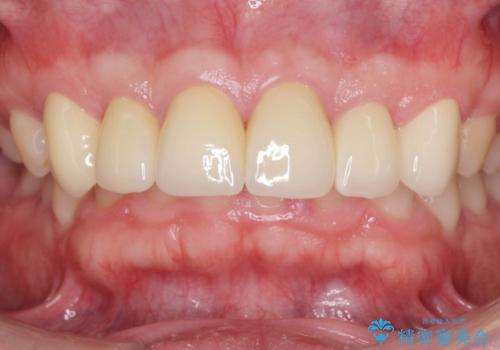

歯周外科を行い、歯ぐきの状態を整えた前歯セラミック治療

歯周外科を行ったことで、歯ぐきの形態や腫れが改善され、審美性だけでなく清掃性も大きく改善することができました。